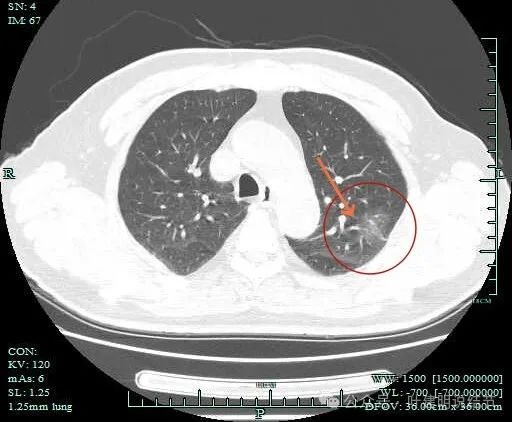

血管进入明显,且灶内端略粗于近心端。病灶内部也有血管穿行。

附近另有血管发出分支进入病灶。

明显血管穿行于灶内。

病灶距斜裂与胸肋面的胸膜都近。